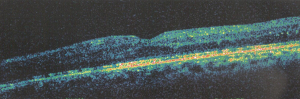

Sei in: Home / edema maculare diabetico trattato con iniezione intravitreale di Taioftal / Schermata 2015-11-28 alle 15.27.21